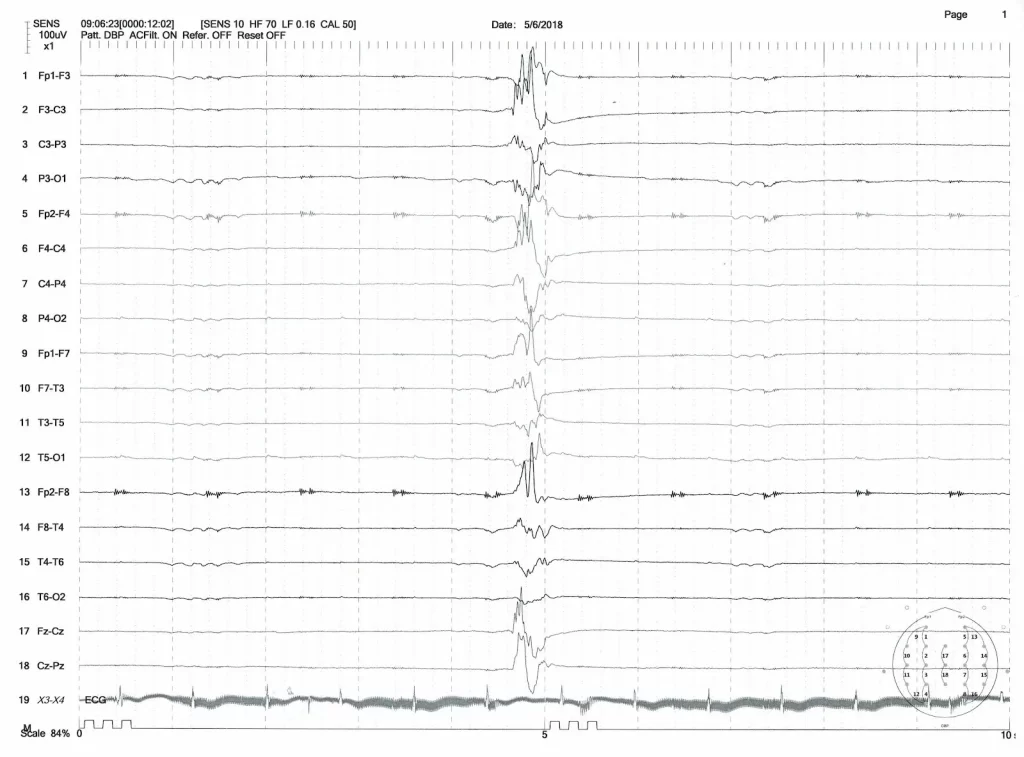

2. 特徴的な脳波(EEG Findings)

- サプレッション・バースト(Suppression-burst): 脳波検査で、激しい電気活動(バースト)と平坦な活動(サプレッション)が交互に現れる非常に特徴的なパターンを示します。これが脳の発達を阻害する大きな要因となります。

- 脳波検査(EEG):

- 前述のサプレッション・バーストやヒプスアリスミアを確認し、臨床的に「早期乳児てんかん性脳症」であると判定します。